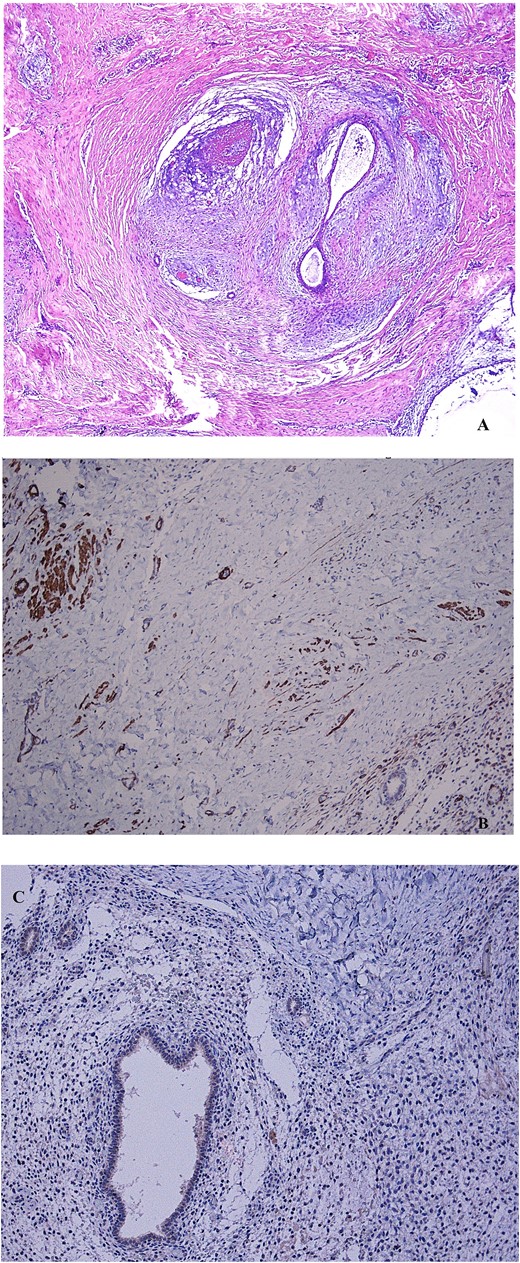

In March, 2022, a 46 year-old woman underwent a laparoscopic supracervical hysterectomy for leiomyomas. Her obstetric history included a cesarean birth 10 years ago. The remaining history was unremarkable. Intraoperatively, no sign of endometriosis was found. Supracervical hysterotomy was carried-out with a monopolar knife. Following placement in a sealed bag, the morcellated uterine corpus was exteriorized through the right iliac port. Pathologic examination confirmed common leiomyomas. In April, 2023, the woman presented to her GP complaining of a cyclically painful suprapubic lump. An ultrasonography scan showed a 4 cm inhomogeneous mass with mild vascularization, extended from the rectus muscle to subcutaneous fat. Magnetic resonance imaging (MRI) confirmed a solid irregularly-shaped mass with high contrast enhancement signal (Fig. 1). To rule-out a malignancy the patient underwent oncologic consultation and a through-cut needle biopsy was performed, yielding a diagnosis of endometriosis. The patient came to gynecological consultation in September, 2023. A hard mass, fixed to the underlying abdominal wall layers just beneath the scar of suprapubic trocar insertion was found at physical examination. We planned continuous oral administration of a Progestogen (Dienogest, 2 mg/day). Within the next two months the patient experienced pain symptoms relief but a mass remaining stable in size was found. In February, 2024, the patient underwent laparotomic excision (Fig. 2). Surgical assessment showed an endometriotic infiltration from subcutaneous tissue to fascia transversalis, sparing the peritoneum. The resection was conducted obtaining at least 5 mm margin-free tissue and later, a fascial mobilization from rectus muscles led to a tension-free primary closure (Fig. 3). Progestogen therapy was continued for six months after surgery. The histopathology confirmed an endometriotic tissue with coexistent smooth muscle-cells proliferation, staining positively to Desmin and negatively to Myogenin immunohistochemistry, leading to the diagnosis of extrauterine adenomyoma (Fig. 4). Six months after surgery, no relapsing disease nor incisional hernia were found.

(A) Non atypical endometrial glands and stroma, surrounded by smooth muscle tissue, representing the mainstay features of adenomyoma, are shown after hematoxylin–eosin stain (4× magnification). (B) The immunohistochemical staining to desmin indicates the muscle cells counterpart of the mass (10× magnification). (C) The negative immunohistochemical staining to myogenin indicates a non-skeletal origin of muscle cells (10× magnification).